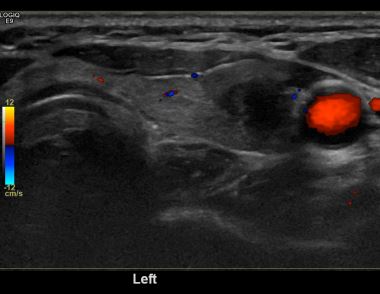

상기환자  외부검사이상소견으로 경과관찰위해 내원하신 50대 중반 여성분으로 의심스러운 갑상선 좌측혹 세포검사진행후 갑상선암으로 진단되었습니다